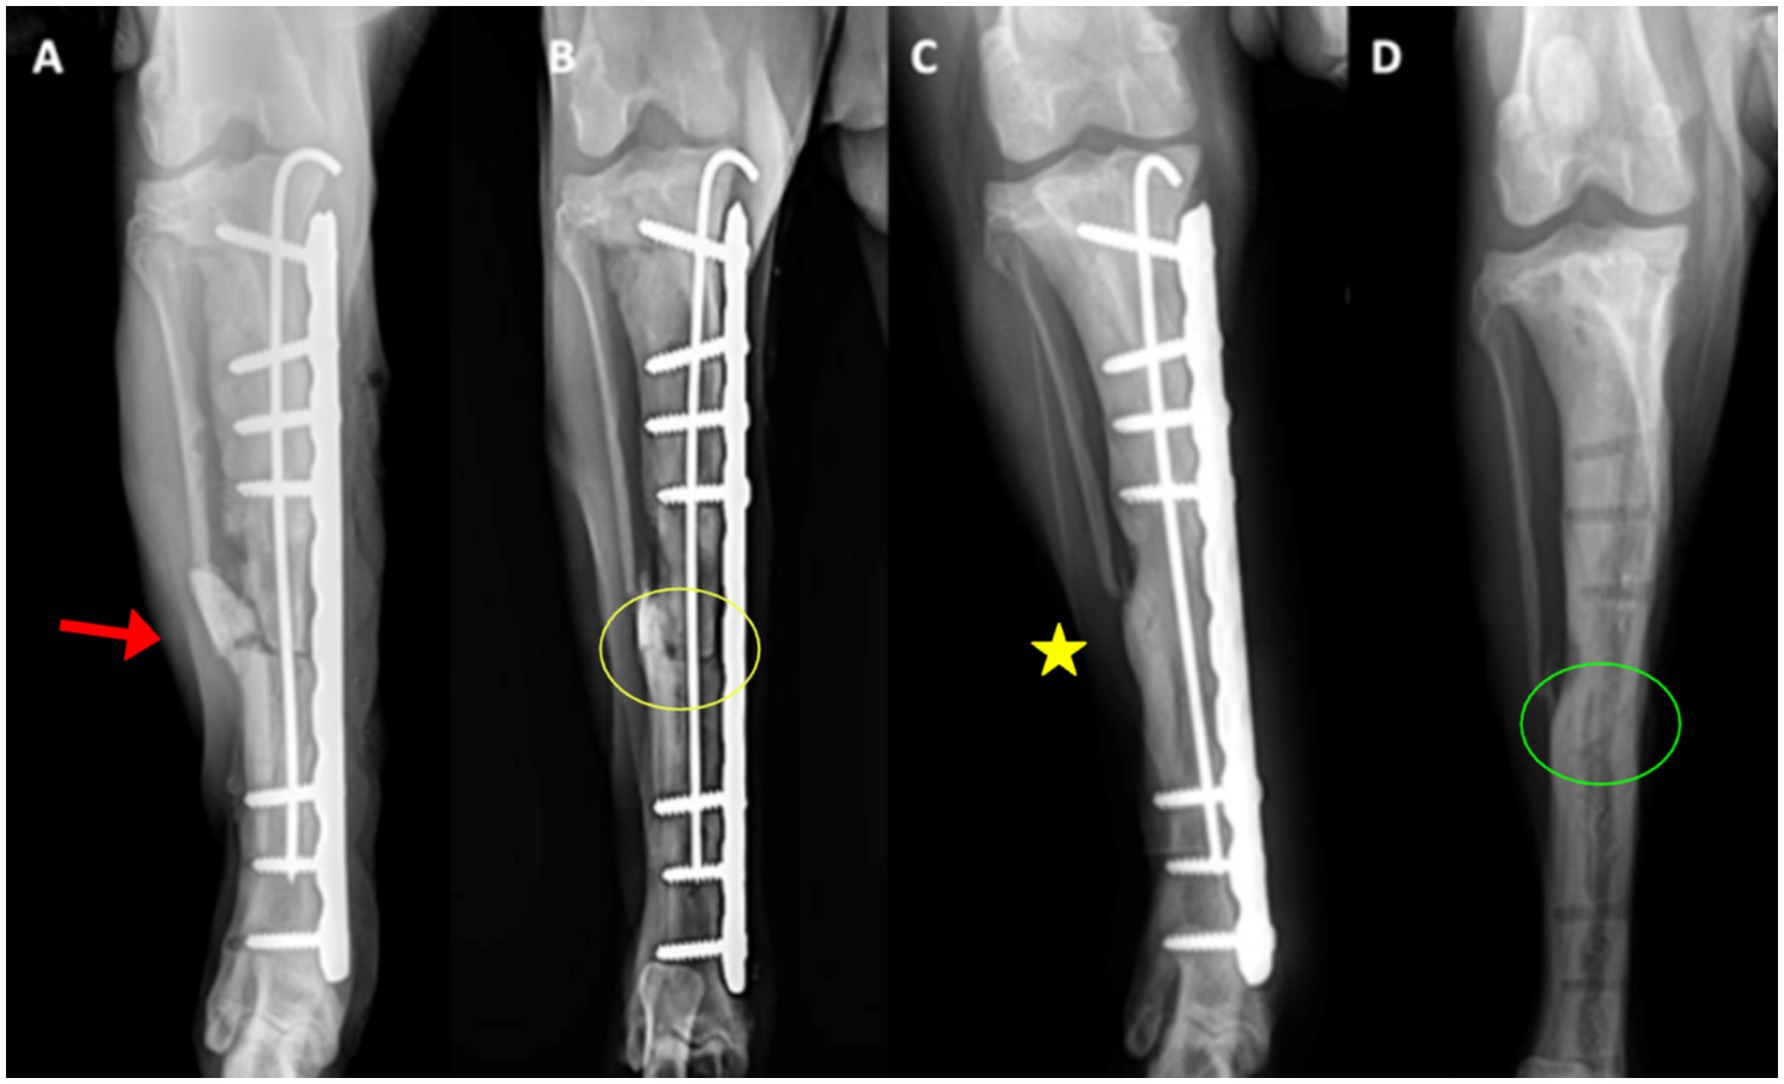

Radiographs at day 0 confirmed correct implant placement and alignment (Figures 3A, 4A). At 8 weeks, bone callus formation and progressive gap closure were evident, without excessive reaction or osteolysis (Figures 3B, 4B). By week 12, the fracture site was fully bridged by a mature callus, with optimal implant positioning and no evidence of osteolysis or inflammation (Figures 3C, 4C). Consequently, implant removal was performed at week 12, with radiographs confirming complete bone healing and restoration of diaphyseal integrity (Figures 3D, 4D).

Figure 3. Craniocaudal radiographs of the right tibia. (A) Immediate postoperative view (day 0) showing correct implant positioning and alignment (red arrows). The osteotomy line is indicated by the arrowhead. (B) At 8 weeks, early callus formation (yellow circle) is visible around the defect, with gradual closure of the fracture gap. (C) At 12 weeks, the bridging callus (yellow asterisk) fully connects the fracture ends, with implants optimally positioned and no osteolysis. (D) After implant removal, the bone defect is completely filled with newly formed bone, restoring diaphyseal continuity (green circle).